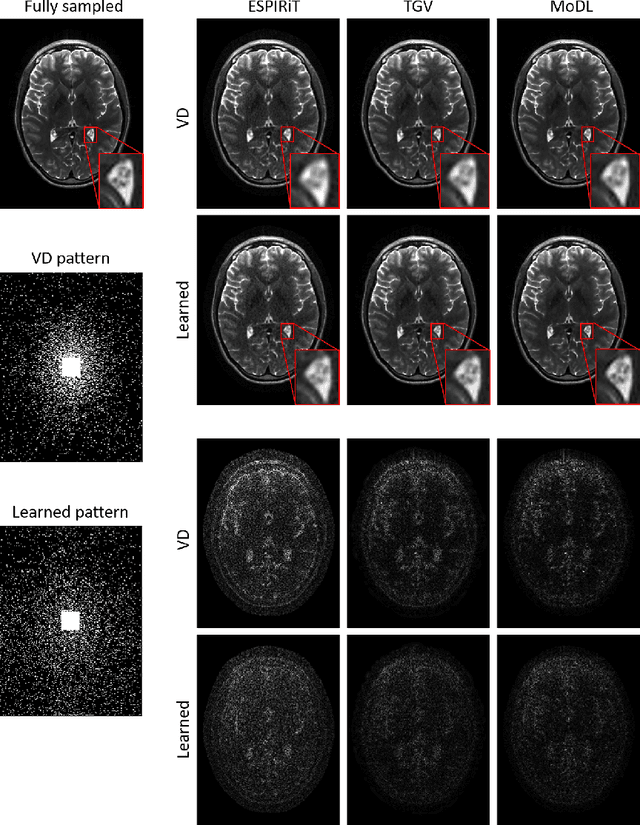

Abstract:The previously established LOUPE (Learning-based Optimization of the Under-sampling Pattern) framework for optimizing the k-space sampling pattern in MRI was extended in three folds: firstly, fully sampled multi-coil k-space data from the scanner, rather than simulated k-space data from magnitude MR images in LOUPE, was retrospectively under-sampled to optimize the under-sampling pattern of in-vivo k-space data; secondly, binary stochastic k-space sampling, rather than approximate stochastic k-space sampling of LOUPE during training, was applied together with a straight-through (ST) estimator to estimate the gradient of the threshold operation in a neural network; thirdly, modified unrolled optimization network, rather than modified U-Net in LOUPE, was used as the reconstruction network in order to reconstruct multi-coil data properly and reduce the dependency on training data. Experimental results show that when dealing with the in-vivo k-space data, unrolled optimization network with binary under-sampling block and ST estimator had better reconstruction performance compared to the ones with either U-Net reconstruction network or approximate sampling pattern optimization network, and once trained, the learned optimal sampling pattern worked better than the hand-crafted variable density sampling pattern when deployed with other conventional reconstruction methods.